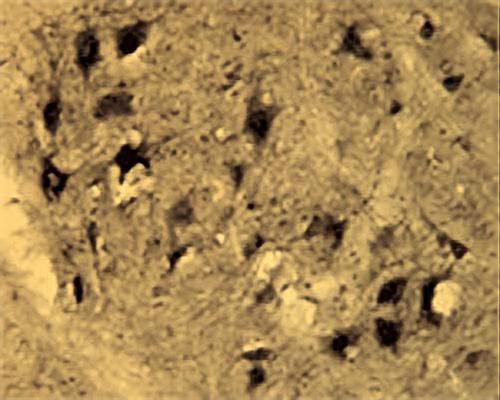

Our Anti-Activity-regulated cytoskeleton-associated protein (Arg3.1) rabbit polyclonal primary antibody detects human, mouse, and rat Activity-regulated cytoskeleton-associated protein (Arg3.1), and is whole serum. It is validated for use in IHC-Frozen.

Arc (also termed activity-regulated cytoskeleton-associated protein or Arg3.1), is an effector immediate early gene whose upregulation has been demonstrated during events of synaptic plasticity. Arg3.1 expression is detectable in neuronal cell bodies and dendrites in the brain regions including striatum and cortex hippocampus, hypothalamus, amygdala.

IHC

IHC: 1:50-1:1000